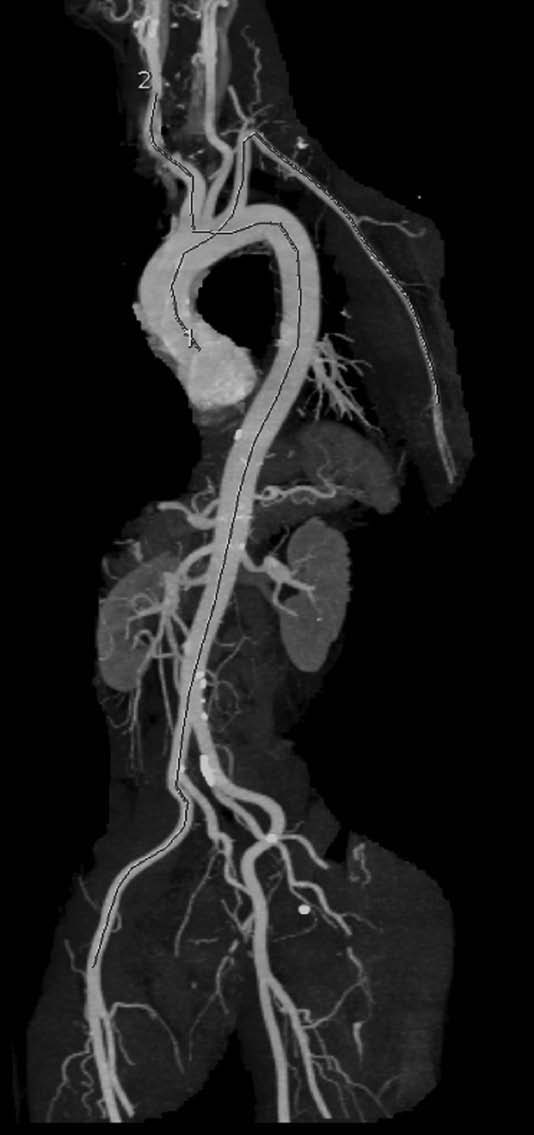

- The pressure wave travels mostly along an aortic segment, including the thoracic descending aorta and the abdominal aorta, and ultimately travels along the iliac and common femoral arteries. This is well exemplified by the Figure, which superimposes the trajectory of the pressure pulse wave on a normal angiogram obtained by magnetic resonance imaging.

The trajectories of the pressure pulse waves along the arterial segments are superimposed onto an angiogram obtained by computed tomography scan (left anterior oblique). The carotid-femoral pathway is described as dotted line, and the QKD pathway is described as dashed line.

Because the stiffness of muscular arteries is little influenced by age and hypertension, Gosse et al8 attributed the difference in QKD duration to ascending aorta and aortic arch. However, a closer look at the Figure shows that the length of the ascending and aortic arch pathway represents a very small part of the total pathway and casts doubt about this statement.